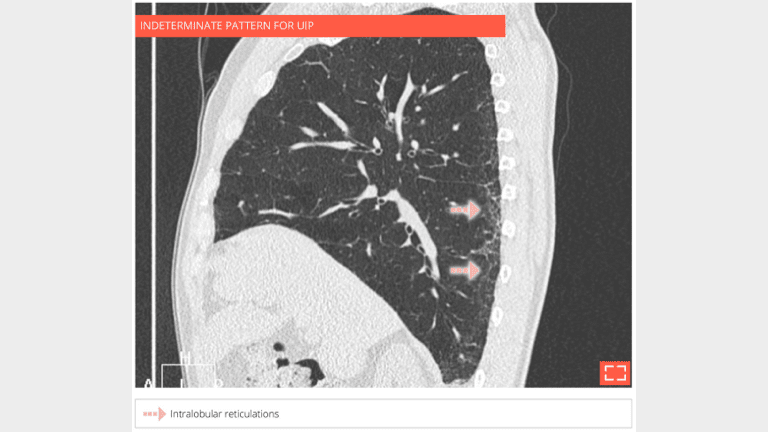

5. Intralobular reticulations

• Isolated and subtle intralobular reticulations, with traction bronchiolectasis.

• No ground-glass opacity or honeycombing.